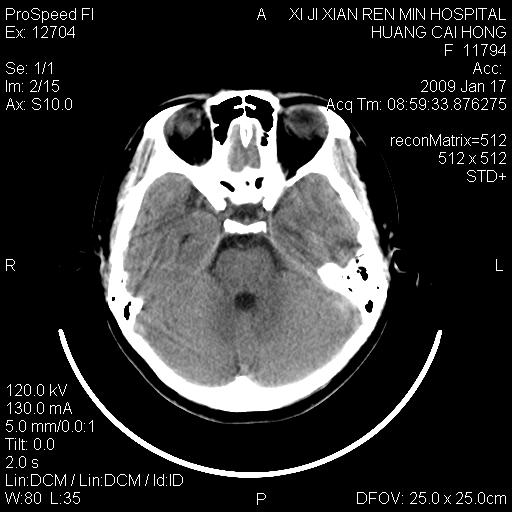

以下是引用zbp537在2009-1-19 13:54:00的发言:[br]首先考虑脑炎。[br]诊断依据:[br]1、患者较年轻。[br]2、有感冒病史。[br]3、左侧颞枕叶这么大一片低密度影,占位征象却不明显,不符合肿瘤特征,其内的高密度影为出血灶。

以下是引用xiaoniu在2009-1-19 13:29:00的发言:[br]左侧颞叶三角形低密度影,占位效应不明显,其内点片样高密都影,青少年患者,首先考虑:少突胶质瘤。因为有感冒病史,不能除外感染的可能。